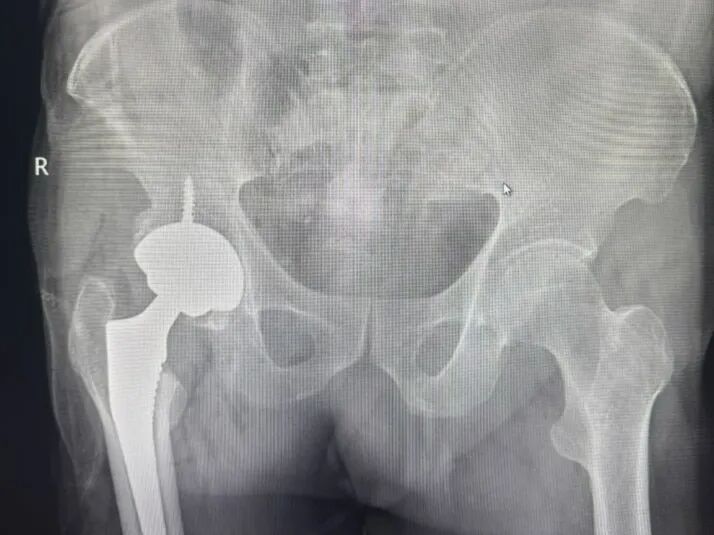

近日,陕西中医药大学附属医院骨伤医院骨病病区成功为一位78岁高龄、曾经历髋部手术的患者完成直接前方入路(DAA)微创全髋关节置换术。该患者王大爷三十年前因股骨颈骨折导致股骨头坏死,此次手术面临髋关节严重骨赘增生、患肢短缩及肌肉组织黏连等复杂情况,属于临床中较为棘手的高龄二次翻修病例。

尽管手术难度较高,在骨伤医院骨病病区团队的精细操作下,王大爷术中生命体征平稳,术后次日即能借助助行器下地行走,未出现并发症,实现了快速康复。

该病例的成功,不仅体现了科室在复杂髋关节置换领域的技术实力,也彰显了团队在处理高龄、多次手术患者方面积累的丰富经验。作为科室王占魁主治医师赴安徽省立医院进修的重要成果转化,本次手术是骨伤医院骨病病区推动技术创新与服务优化的一次生动实践。未来,骨伤医院骨病病区将继续聚焦复杂髋关节病变的诊疗与研究,强化术后康复支持,为高龄、多次手术等特殊患者群体提供更安全、更精准、更高效的医疗解决方案。